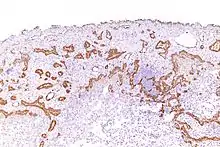

Mesothelioma

Using immunohistochemistry, calretinin can be demonstrated in both benign mesothelium and in malignant mesothelioma[12][13] and can be used to help differentiate different lung tumours.[14] Antibodies to calretinin can also be used to distinguish between different types of brain tumour, demonstrating only those with neuronal rather than glial, differentiation.[15] Furthermore, the essential function of calretinin in mesothelioma cell lines has been demonstrated in vitro and may be an interesting target for therapeutical approaches.[16]